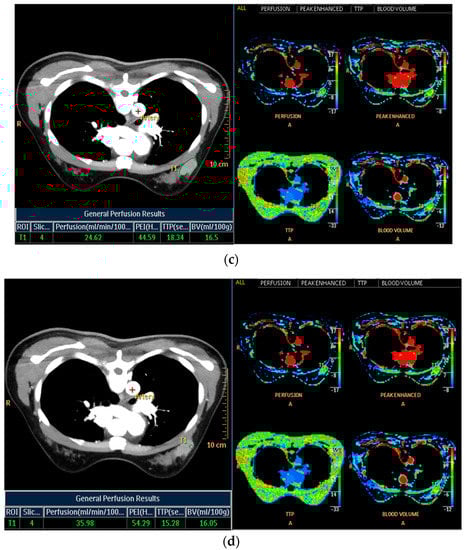

Histogram analysis on CT was performed on pre- and postcontrast images using the same method as on MRI (Figure 3a,b). When the tumor was maximally enhanced, an ROI containing the entire tumor was drawn []. In perfusion analysis on CT, similarity to MRI, two ROIs, total tumor area and hot spot were measured. In addition, time–intensity curves and perfusion color maps for the tumors were measured automatically when we drew ROIs. Four parameters on CT perfusion maps were measured from the two ROIs for each cancer: (a) perfusion (blood flow; mL/min per 100 mL), (b) blood volume (total blood volume over the region during the scan period; mL/100 g), (c) peak enhancement intensity (peak enhancement after contrast media injection; Hounsfield units [HU]), and (d) time to peak (time to reach peak contrast enhancement; seconds; Figure 3c,d).

Figure 3.

Histogram and perfusion analyses on breast CT in a 42-year-old woman with a 30 mm triple-negative invasive ductal carcinoma of the left breast (the same patient as Figure 2). (a,b) Histogram analysis on CT: Axial contrast-enhanced low-dose CT shows an oval shaped, irregular marginated, and heterogeneous enhancing mass. Histogram analysis on CT was performed using the same method on MRI. (c,d) Perfusion analysis on CT: Two ROIs (ROI1: entire tumor and ROI2: hot spot) were manually delineated and four perfusion parameters from each ROI were obtained, perfusion, peak enhancement intensity (PEI), time to peak (TTP), and blood volume (BV).